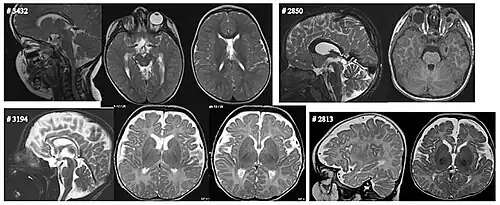

Chromosoom 3

Een de novo deletie van 1,69 Mb (chr3:182.649.000–184.339.000 equivalent aan hg19 chr3:181.166.306–182.856.306) resulteerde in een verlies van een enkele kopie van SOX2, weergegeven in rood. Deleties zijn gemarkeerd met rode balken. Genomische coördinaten zijn gebaseerd op de Human Genome Assembly (NCBI36/hg18) van maart 2006. Deze deletie veroorzaakte tweezijdige anoftalmie. Zie afbeelding (a).

Chromosoom 13

Trisomie van chromosoom 13 veroorzaakt het syndroom van Patau met relatief vaak anoftalmie.

Chromosoom 14

Een deletie van 6,5 Mb in CaseID 3000 (chr14:56.094.000–62.594.000; equivalent aan hg19 chr14:57.024.247–63.524-247) en een de novo deletie van 455 kb in CaseID 3346 (chr14:56.224.000–56.679.000; equivalent aan hg19 chr14:57.154.247–57.609.247) veroorzaakten tweezijdige anoftalmie. Zie afbeelding (b).

Een tussenliggende deletie op chromosoom 14 is soms ook de oorzaak van anoftalmie. De deletie van dit chromosoomgebied is ook in verband gebracht met patiënten met een kleine tong en een hoog gehemelte, ontwikkelings- en groeiachterstand, niet ingedaalde (cryptorchisme) teelballen met een micropenis en hypothyreoïdie. Het gebied dat verloren is gegaan is gebied q22.1-q22.3. Dit bevestigt dat regio 22 op chromosoom 14 de ontwikkeling van het oog beïnvloedt.[20]